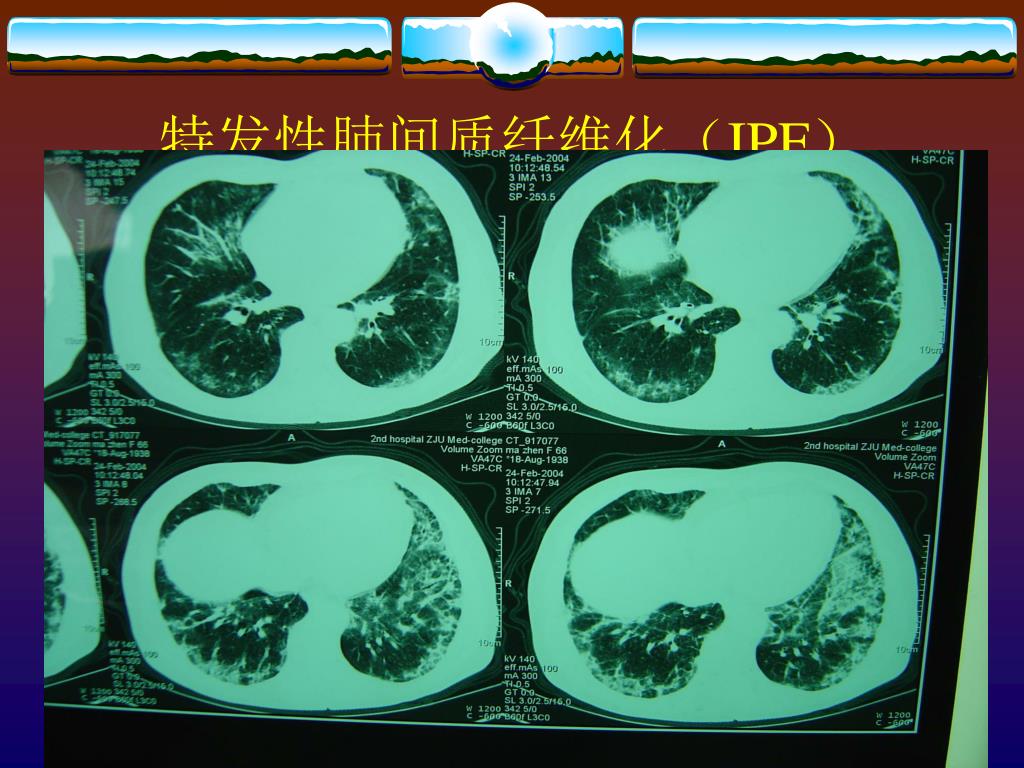

12. 特发性肺间质纤维化(IPF)

13. HRCT 早期 IPF

14. 蜂窝肺

15. HRCT 晚期 IPF Slide courtesy of G Raghu, MD.